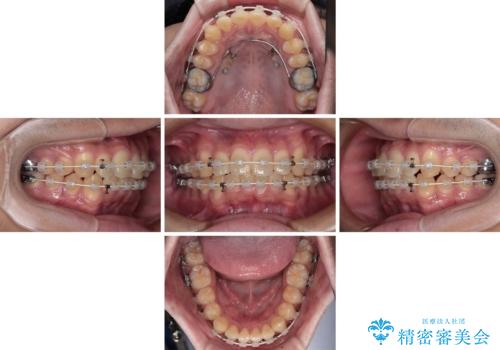

- 矯正装置

- 審美装置

- 1年6ヶ月

- 10-30回